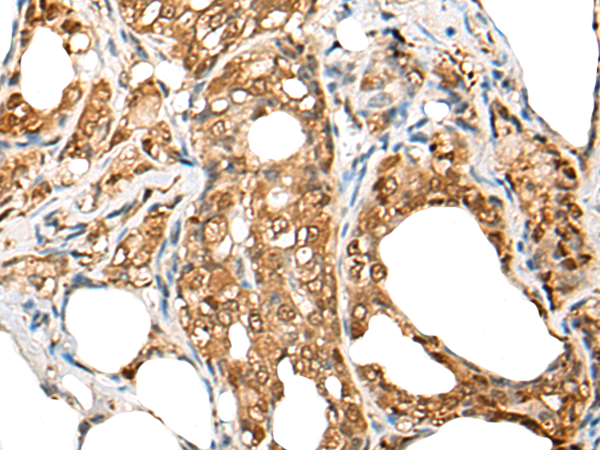

IHC positive control:

Human esophagus cancer and Human colorectal cancer

IHC Recommend dilution:

25-100